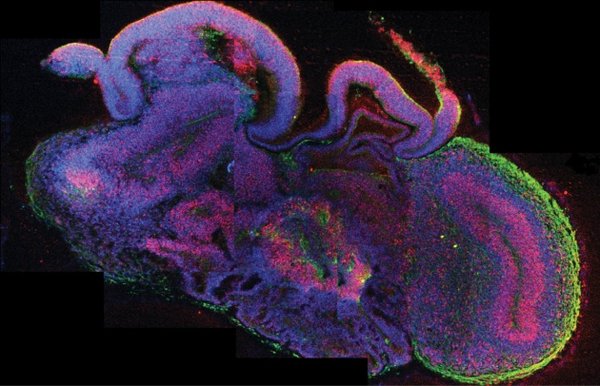

Giza garun txiki funtzionalak lortu dituzte, saguei transplantatuta

Osasuna

2018ko mai. 10a, 00:00